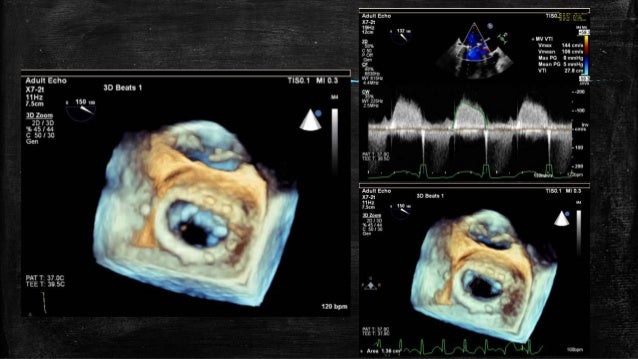

Echocardiography is the potential in providing in-depth and thorough comprehensive profiling of both the structural, morphological, anatomical, and hemodynamic changes which are induced and aggravated by either acute or chronic CAD.

To date, Echocardiography is a first-line investigation to detect cardiac disorders. The identification of patients with myocardial ischemia is an integral part of the diagnosis of CAD. A lot of arrangements should be and can be made at different stages of health care services to combat this life killer through early diagnosis and consequent therapeutic and preventive strategies.ĬAD is regarded as the most common fatal disease all over the world. Though the efforts of prevention of cardiovascular disease at primary, secondary, and tertiary levels are mandatory, diagnostic modalities at this regard need to be re-visited and re-evaluated from various contexts. More than 600,000 Americans die from cardiac or heart disease every year, leading to one in every four deaths at the statistical level. Other significant cardiac disorders are valvular disorders, congenital heart diseases, and others. Characterized by atherosclerosis in the arteries, coronary artery disease (CAD) is the most common heart disease which is also the most frequent cause of heart attack. The term “heart disease or cardiac disorders” refers to several conditions where heart functions or structures are impaired and abnormal.

It is a retrospective study for data record review as an observational study, so no trial registration is required.Ĭardiovascular diseases are the most common cause of disability and mortality worldwide, with a prevalence of 126 million persons affected globally (1655 per 100,000) and 17.9 million mortalities making it 31% of all global deaths. Trial Registration: The research doesn’t include experiments in humans or animals. Gender differences and age stratification also contributed to this differential pattern of diagnosis. Both investigations showed a differential pattern in cardiac disorders diagnosis with a particular focus on IHD. Conclusions: In conclusion, both techniques, namely standard Echocardiography, and myocardial scintigraphy, are useful in the evaluation and detection of cardiac disorders in patients having any type of cardiac problems. Scintigraphy showed a higher detection rate (59%), while only 29% of cases were detected with IHD by eco-cardiograph. The age stratification did not impact the prevalence of cardiac disorders detected by them. Results: About 84% of cases were diagnosed with any types of cardiac disorders by Echocardiography, whereas through scintigraphy, 61% of patients were detected cardiac disorders. All subjects underwent gated myocardial perfusion scintigraphy and standard Echocardiography. Methods: 157 patients (male/ female: 68%/32% mean age 64 ± 0.83 years) were included in the report in the current study. Aim: The current study aimed to compare the effectiveness of echocardiographic and scintigraphy investigation in cardiovascular disorders detection and evaluation, including ischemic heart disease (IHD) diagnosis at King Abdulaziz University in Saudi Arabia. Background: Cardiac disorders are the leading causes of morbidity and mortality globally.